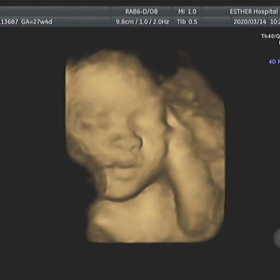

【4Dエコー動画あり】27w4d & 30w4d & 32w5d 妊婦健診の記録